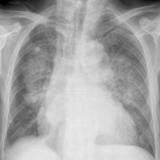

APE 1

Date: 11/05/2005

Views: 4072